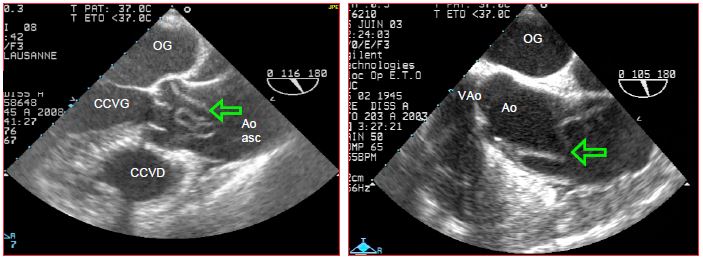

Chaque zone présente des problèmes spécifiques. Les pathologies chirurgicales de l'aorte thoracique se divisent en cinq types de lésions, qui sont par ordre de fréquence: la dissection, l'anévrysme, l'athéromatose, la rupture traumatique et la coarctation. Les lésions réclamant un traitement urgent sont regroupées sous le terme de syndrome aortique aigu ; elles comprennent la dissection, la rupture traumatique, la rupture d'anévrysme, l’athérome perforant et l’hématome intramural [2].